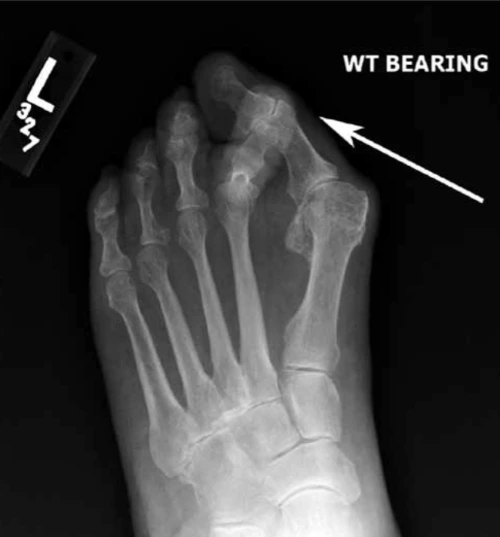

발 구조 외에도 생활습관, 유전, 기계적인 스트레스가 무지외반증을 만드는 주범이다. 먼저 생활습관에 대해서 알아보자. 가장 대표적인 건 신발 선택이다. 폭 좁고 앞코가 뾰족한 신발, 하이힐 같은 것들이 발가락을 비틀고 엄지발가락 관절에 지나치게 압력을 준다. 하이힐은 특히 체중을 앞으로 쏠리게 해 발 앞부분에 부담이 집중된다. 심한 경우, 엄지발가락이 두 번째 발가락과 겹치는 크로스오버 사인(crossover sign)이 나타나기도 한다.

AD_4nXd3Zs74c1csuXceEmo86NQ3PhrNh4TrRdndkoV2WwcgatiCIuBTeJKH2elHDgHBBOa0Wu_76-2n6Z-0mbt8T3VgZMhU2yHXhDGwZ9svYSs8_VEIXu9k9B7RS7hU_pwpyQSEyZtNBg?key=AhLvapB3KLbFMHGKEOaM91Xy [그림 3] 크로스오버 사인(crossover sign). 심한 무지외반증으로 인해 엄지발가락과 두 번째 발가락이 겹쳐진 모습